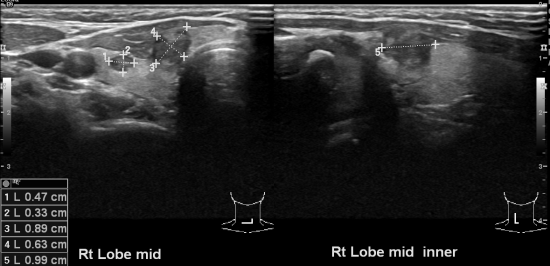

PET scan상 이상소견 있어 본원에서 갑상선초음파 실시하여 세포검사통해

유두암으로 진단되신 39세

여자분입니다.